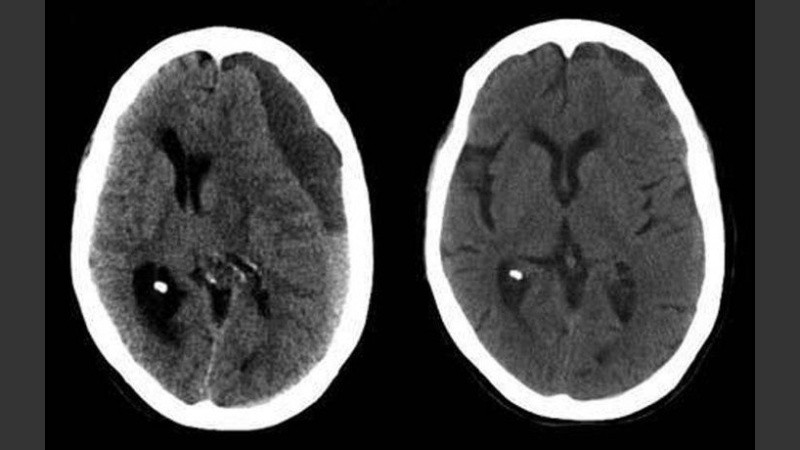

En 2013, la expresidenta Cristina Fernández de Kirchner, fue operada en la Fundación Favoloro, luego de que se le detectara la misma afección, un hematoma subdural, tras presentar un cuadro de cefaleas.

El propio ministro confirmó que tiene la misa afección por la que fue operada Cristina e incluso bromeó: "No es por disciplina partidaria".